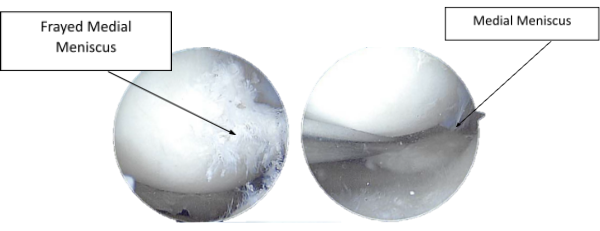

An arthroscopic surgery was performed. The probe was inserted on the medial portal and the posterior horn of the medial meniscus was examined. It showed a complex tear up to tie periphery.

There were degenerative changes in the meniscus with calcification. The tear was not repairable. A decision for meniscectomy was taken and the meniscus was debrided and cleaned up to the stable edges using shaver and punch.

Figure 2.1. Intraoperative Arthroscopy Images